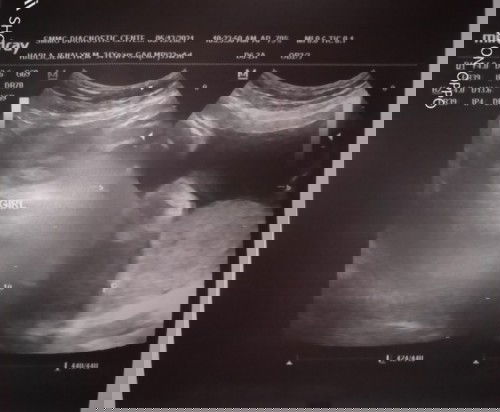

#pregnancy hi mga momshies ask ko lng Kung Hindi ba dapat Ako mag-worry kasi Sa Ultrasound ko ang due date ko June 16 .. Pero Sa check up sakin Sa health centre June 26 pa .. ? overdue na ba ko ?